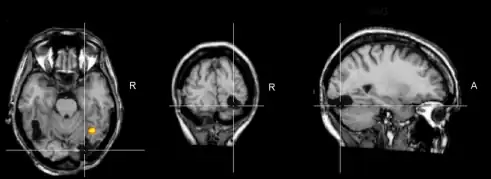

| The fusiform face area, the part of the brain associated with facial recognition | |

Prosopagnosia, more commonly known as face blindness,[2] is a cognitive disorder of face perception in which the ability to recognize familiar faces, including one's own face, is impaired, while other aspects of visual processing (e.g., object discrimination) and intellectual functioning (e.g., decision-making) remain. The term originally referred to a condition following acute brain damage (acquired prosopagnosia), but a congenital or developmental form of the disorder also exists, with a prevalence of 2.5%.[3] The brain area usually associated with prosopagnosia is the fusiform gyrus,[4] which activates specifically in response to faces. The functionality of the fusiform gyrus allows most people to recognize faces in more detail than they do similarly complex inanimate objects. For those with prosopagnosia, the method for recognizing faces depends on the less sensitive object-recognition system. The right hemisphere fusiform gyrus is more often involved in familiar face recognition than the left. It remains unclear whether the fusiform gyrus is specific for the recognition of human faces or if it is also involved in highly trained visual stimuli.